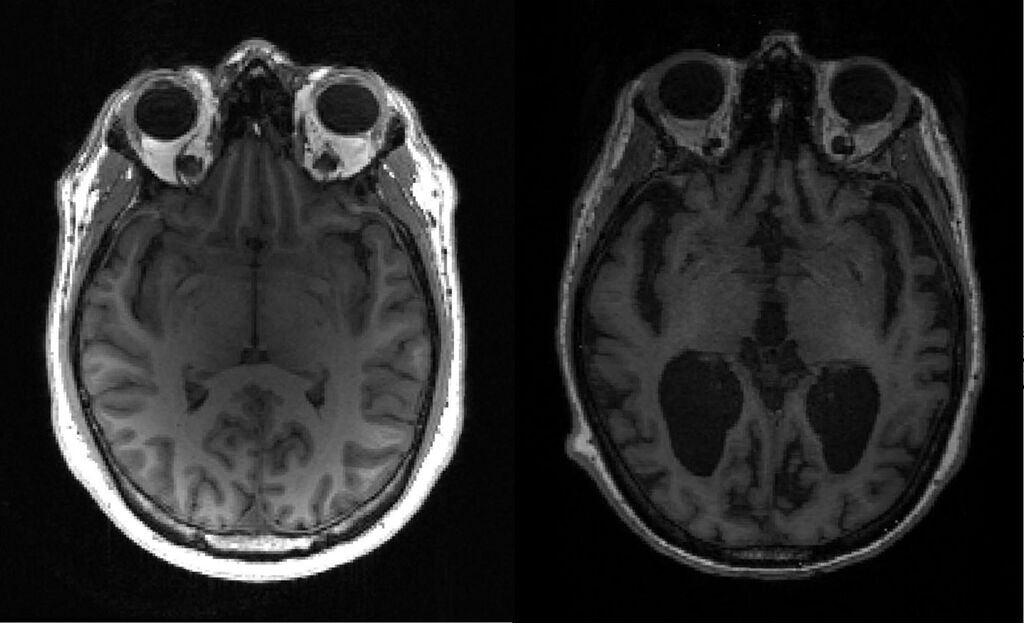

![]() |

| Image non datée montrant un cerveau sain et un cerveau atteint par la maladie d'Alzheimer. |

| Photo : AFP/VNA/CVN |